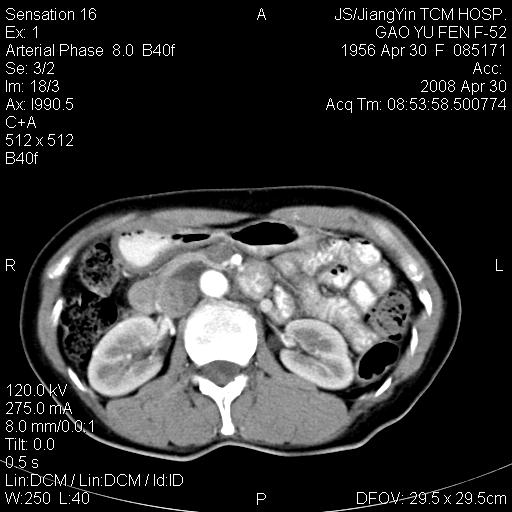

标题: CT13307:肠系膜囊肿? [打印本页]

标题: CT13307:肠系膜囊肿?

囊性淋巴管瘤可能比较大。

良性囊性占位,来源于肠系膜的可能性大

图像少,不能连续起来看,不太敢确定囊肿前方的条状结构是十二指肠水平段?如果是,那肠系膜囊肿,淋巴管瘤都有可能。

病变位于肾静脉后方,支持腹膜后占位性病变,以囊性淋巴管瘤可能性大.